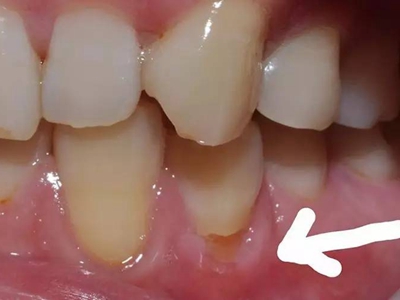

楔状缺损症状图片

楔状缺损是一种非龋性牙颈部慢性损伤,是指发生在牙齿唇、颊面颈部的慢性硬组织缺损。典型缺损由两个夹面组成,口大底小,呈楔形。楔状缺损多发生于中老年人,主要原因是刷牙不当,防治措施是调整咬合关系,改善刷牙方法,配合相应的治疗。

楔状缺损与年龄相关,即年龄越大,缺损越重,患者多有横刷牙习惯,患牙为多颗甚至全口,常以口角附近的牙齿(尖牙、前磨牙)为重。典型表现为牙颈部缺损,呈楔形,由两个夹面组成,口大底小,缺损处质地坚硬,表面光滑,边缘整齐,无染色,轻微泛黄常为牙齿本色,严重时可导致牙髓腔暴露甚至牙齿横向折断,根据缺损深浅不同,可伴有牙齿敏感甚至疼痛。

不正确的刷牙方法,尤其是横刷法是发生楔状缺损的主要原因,因为牙颈部结构比较薄弱,易发生磨损。另外,颊面牙颈部是咬合应力集中区,长期的咀嚼压力使牙体组织疲劳,应力集中区出现破坏,也会造成楔状缺损。龈沟内酸性渗出物,也与楔状缺损的发生有关。